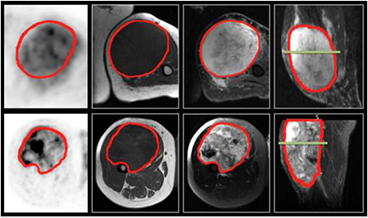

Most tumours do not represent a homogeneous entity, but rather are composed of multiple clonal sub-populations of cancer cells forming complex dynamical systems that exhibit rapid evolution as a result of different therapy perturbations. In solid cancers such as STSs, the tremendous extent of heterogeneous characteristics is expressed at multiple levels. Genes, proteins, cellular microenvironments, tissues and anatomical landmarks within tumours exhibit considerable spatial and temporal variations that could potentially yield valuable information about tumour aggressiveness. However, studying tumour heterogeneity using histopathological samples from biopsies is very difficult since the procedure is invasive and the information obtained may vary depending on which part of the tumour is sampled (Longo 2012). This issue is addressed by the new emerging field of 'radiomics', which refers to the extraction and analysis of large amounts of information from medical images using advanced quantitative feature analysis (Kumar et al 2012, Lambin et al 2012). The central hypothesis of radiomics is that the genomic heterogeneity of aggressive tumours could translate into heterogeneous tumour metabolism and anatomy, a concept demonstrated by Segal et al (2007) and Diehn et al (2008), and recently verified by Aerts et al (2014). Diagnostic images could thus reveal important prognostic information about disease risk. In this work, we attempt to quantify intratumoural heterogeneity in STSs using texture analysis performed on 2-deoxy-2-[18F]fluoro-D-glucose (FDG) positron emission tomography (PET) and magnetic resonance imaging (MRI). Figure 1 depicts how functional FDG-PET and anatomical MR imaging information together reflect the heterogeneous sub-region characteristics of aggressive STSs.

Figure 1. FDG-PET and MRI diagnostic images of two patients with soft-tissue sarcomas of the extremities. Top row: patient that did not develop lung metastases. Bottom row: patient that eventually developed lung metastases. 1st column: FDG-PET images, axial plane. 2nd column: T1-weighted images, axial plane. 3rd column: T2-weighted fat-saturated images, axial plane. 4th column: short tau inversion recovery images, sagittal plane. The green lines in the two images of the 4th column correspond to the plane shown in the three other respective images.